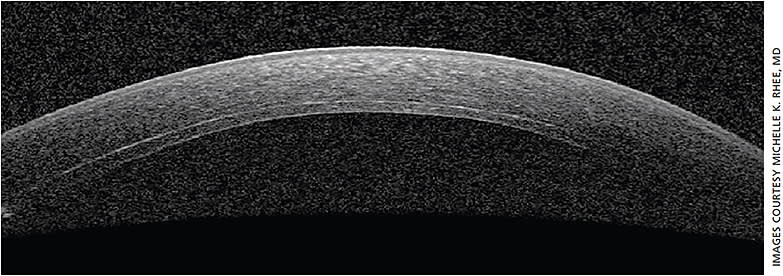

In preparation for the possibility of DSEK, consider a target postoperative refraction at about -0.75 D to -1.00 D since DSEK tends to produce a hyperopic shift in the +1.25-D range. DMEK (typically 15 μm thick and planar in configuration) also has a hyperopic shift, but less so than DSEK since there is no posterior stroma transplanted.